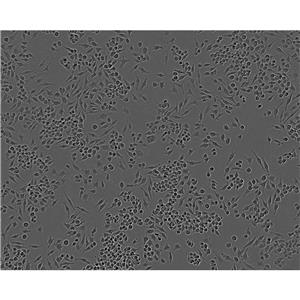

人神经胶质细胞瘤细胞是一种肿瘤细胞,起源于神经胶质细胞。该细胞可以被用于研究神经胶质细胞瘤的生物学特征、药物筛选和肿瘤治疗等。

神经胶质细胞瘤是最常见的神经系统的肿瘤,其中胶质母细胞瘤是一种恶性胶质瘤,是成人最常见的颅内恶性肿瘤。U251细胞属于胶质母细胞瘤细胞系,该细胞具有贴壁生长的特征,并且在适当的培养条件下可以维持肿瘤细胞的恶性表型。

U251细胞可以用于研究神经胶质细胞瘤的生物学特征,如细胞增殖、迁移、侵袭、细胞周期和细胞凋亡等。此外,U251细胞还可以用于药物筛选和肿瘤治疗的研究,如化疗药物筛选、放疗效果评估和基因治疗等。